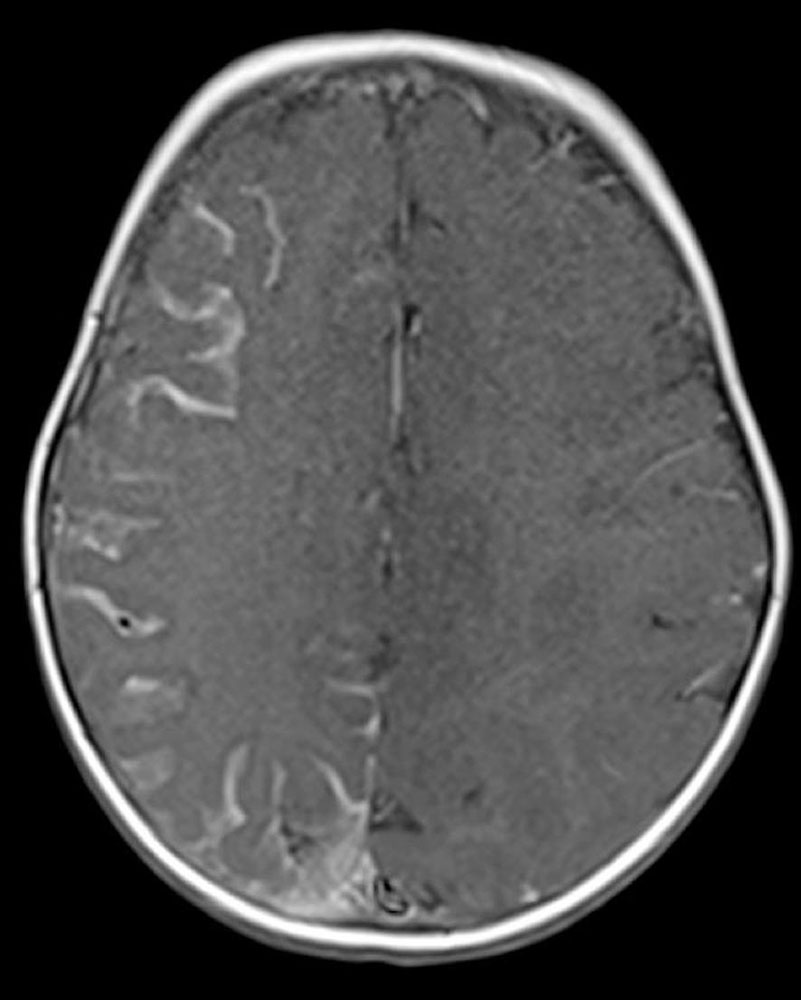

| Facial + leptomeningeal CM + ocular abnormality +/- overgrowth of bone or soft tissue | Sturge-Weber syndrome |

| Macrocephaly CM/megalencephaly CM polymicrogyria (MCAP) | M-CAP syndrome |